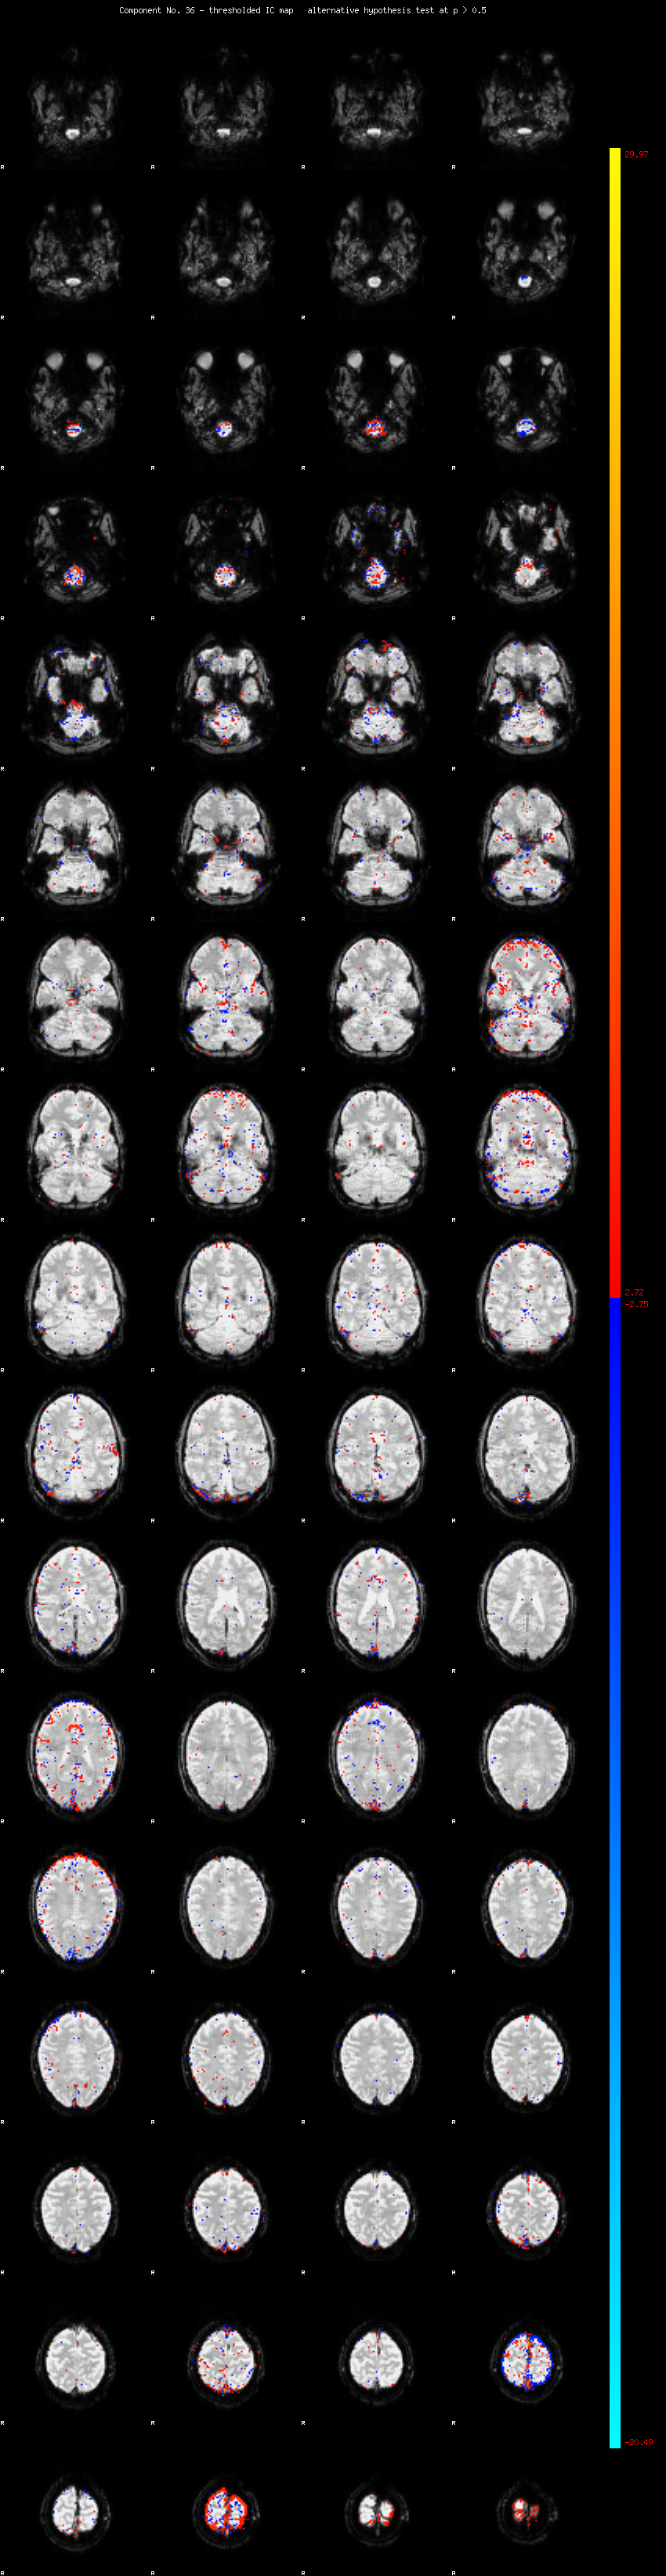

MELODIC Component 36

1.14 % of explained variance;     0.76 % of total variance